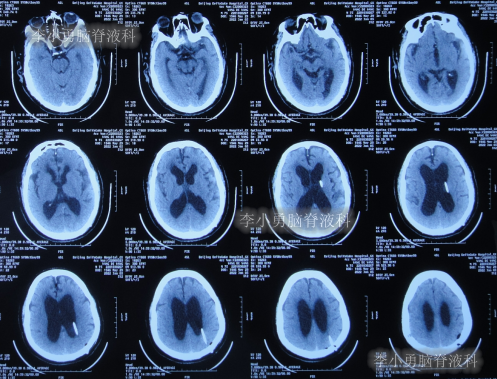

2020年10月29日(发病已8年),因症状一直没有得到改善且呈进行性加重趋势,查头部核磁示脑积水(图-1)。

图-1:2020年10月29日头部核磁